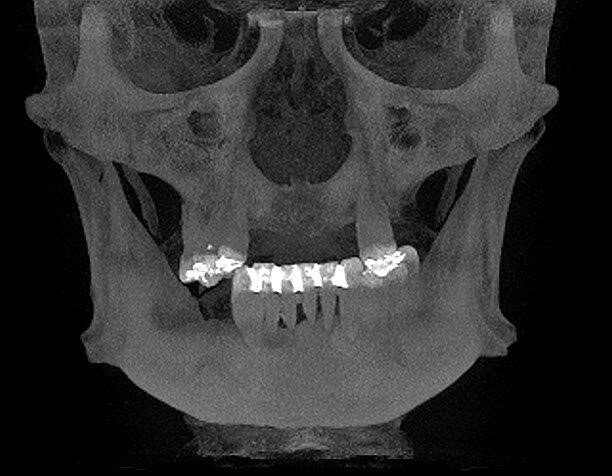

Wykonano CBCT, z którego wynikało, iż pacjent ma chorobę przyzębia. Zakwalifikowano wszystkie 10 zębów żuchwy do ekstrakcji. Zaplanowano zaopatrzenie pacjenta 8 implantami ICX oraz 5 implantami tymczasowymi Alpha Bio w celu wykonania pracy protetycznej tymczasowej bez obciążenia implantów docelowych ze względu na brak kontroli nad pacjentem w okresie wgajania implantów (zdjęcie CBCT oraz wewnątrzustne pacjenta). Za pomocą komputerowego systemu nawigacyjnego 3D został zaprojektowany szablon przytwierdzany 3 pinami do kości żuchwy w celu jego stabilizacji.

Następnie przytwierdzono ponownie szynę i kolejnymi wiertłami zaopatrzonymi w stopery rozpoczęto preparację łoża dla implantów. Podczas pracy pozyskiwano kość własną pacjenta w celu późniejszej augmentacji. Po przygotowaniu wszystkich miejsc implantacyjnych przystąpiono do wprowadzenia wszystkich 8 implantów poprzez tuleje w szablonie, a następnie usunięto szablon z jamy ustnej pacjenta i założono śruby gojące. Kolejnym etapem pracy było wprowadzenie 5 implantów tymczasowych oraz zaopatrzenie zębodołów poekstrakcyjnych materiałem kostnym własnym pacjenta zmieszanym z materiałem ksenogennym i osoczem. Augmentat pokryto błonami PRF i zaszyto śluzówkę. Wprowadzono antybiotykoterapię. Wykonano zdjęcie CBCT kontrolne po zabiegu.